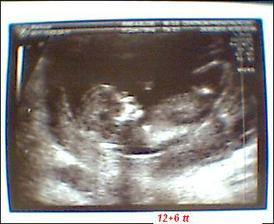

● 24.3. NT+ screening z UTZ vyšel perfektně všechno dopadlo v pořádku i srdíčko a průchodnost jsme viděli nosní kůstku, šíjové projasnění bylo 1,4 mm taky v pořádku. Mimi se nechtělo fotit museli jsme ho budit ale nakonec hezká fotka z toho vyšla a máme 6,5 cm délku. Ještě počkáme na krev a bude to. Výsledky z krve na dawnův syndrom 1:43 000 takže negativní vše ok 😀 . Změna termínu porodu na 30.9.2010 takže jsme 12+6 tt